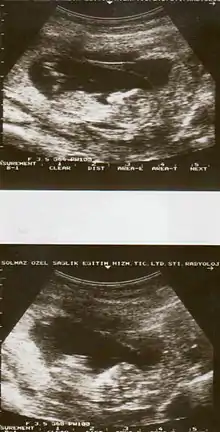

Ultrasound showing placental abruption.

Placental abruption is suspected when a pregnant mother has sudden localized abdominal pain with or without bleeding. The fundus may be monitored because a rising fundus can indicate bleeding. An ultrasound may be used to rule out placenta praevia but is not diagnostic for abruption. The diagnosis is one of exclusion, meaning other possible sources of vaginal bleeding or abdominal pain have to be ruled out in order to diagnose placental abruption.[5] Of note, use of magnetic resonance imaging has been found to be highly sensitive in depicting placental abruption, and may be considered if no ultrasound evidence of placental abruption is present, especially if the diagnosis of placental abruption would change management.[14]